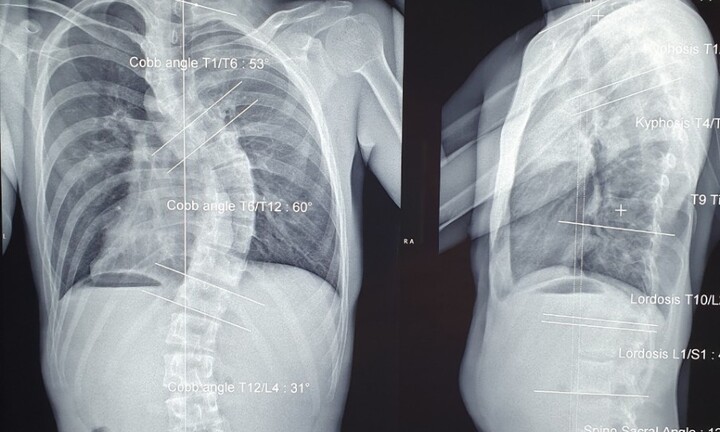

Hiện nay, những ca trẻ bị gù, vẹo, cong cột sống mức độ nặng đến điều trị ngày càng gia tăng, đây là tình trạng đáng báo động.